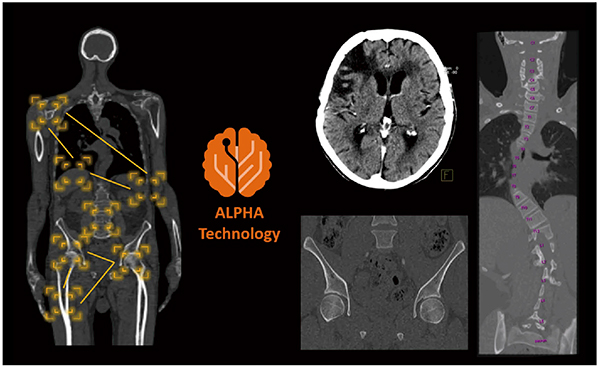

撮影準備段階では,AIを用いて開発された「FAST 3D Camera」を活用することで,誰でも簡単に,精度高く自動ポジショニングを行うことができます(図2)。FAST 3D Cameraは,寝台の上部にあるカメラから患者の形状,位置,高さ情報を三次元データとして取得します。また,赤外線測定データを同時に取得し,ディープラーニングを利用して開発された技術によって,人と比較して誤差やバラツキが少なく,頭部,胸部,腹部領域などでは平均数mmの誤差で,正確な患者ポジショニングが可能となっています1)。撮影段階では,“FAST Planning”が位置決め画像を解剖学的に自動認識し,患者個々に適切な撮影範囲を提示します。また,“Check&Go”が体外金属の有無を自動判別して,撮影前に取り外し忘れを防ぐことで,画像クオリティを保ちつつアーチファクトなどを極力抑えるよう,オペレータをアシストします。撮影後の画像再構成段階では,“ALPHA (Automatic Landmarking and Parsing of Human Anatomy) Technology”が患者個々の解剖学的なランドマークを認識し,自動で頭部OM(orbitomeatal)ラインや股関節などの軸位に沿うような角度に調整してMPR画像を作成します(図3)。ALPHA Technologyは,数百のサンプル画像データを基に専門家が必要とする解剖学的ランドマークとそれを囲む関心領域から画像パターンを検出するトレーニング(機械学習)を行い,多くの解剖学的部位をデータベース化しています2),3)(図4)。トレーニングから得られたデータベースを使用することで,新規に撮影されたCT画像に対して解剖学的なランドマークを自動検出し,当該部位の軸位に沿った角度に自動調整された画像を作成できます。Investigative RadiologyにてNishiiらは,ALPHA Technologyを使用することで,781例の頭部CT画像のうち99.7%でOMラインに自動角度調整したaxial画像が正確に得られ,かつ画像作成までの時間はCTスペシャリストである技師と比較して4倍,1年目の技師と比較して8倍速かったと報告しています4)。ALPHA Technologyを用いることで,誰もが簡単に解剖学的な角度に調整された画像を短時間で得ることができます。

図3 ALPHA Technologyを用いて作成したMPR画像

患者個々の解剖学的なランドマークを認識し,自動的に当該部位の軸位に沿った角度に調整してMPRを作成できる。

図4 ALPHA Technologyの開発

ALPHA Technologyの開発は,サンプル画像データを基に専門家が機械学習を用いてトレーニングした知識データベースを構築。